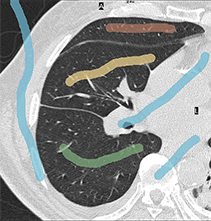

Distinct intensity appearances and smooth contrast-aligned boundaries are standard segmentation cues. However, in most real applications of image segmentation there are multiple objects of interest with similar or overlapping color appearances. Intensity edges also could be cluttered or weak. These common practical problems require additional regularization, as illustrated in the second row of Figure 1.

| two examples of images with seeds (medical and photo) | |

| multi-object segmentation using Potts model | |

| multi-object segmentation adding our hedgehog shapes prior | |